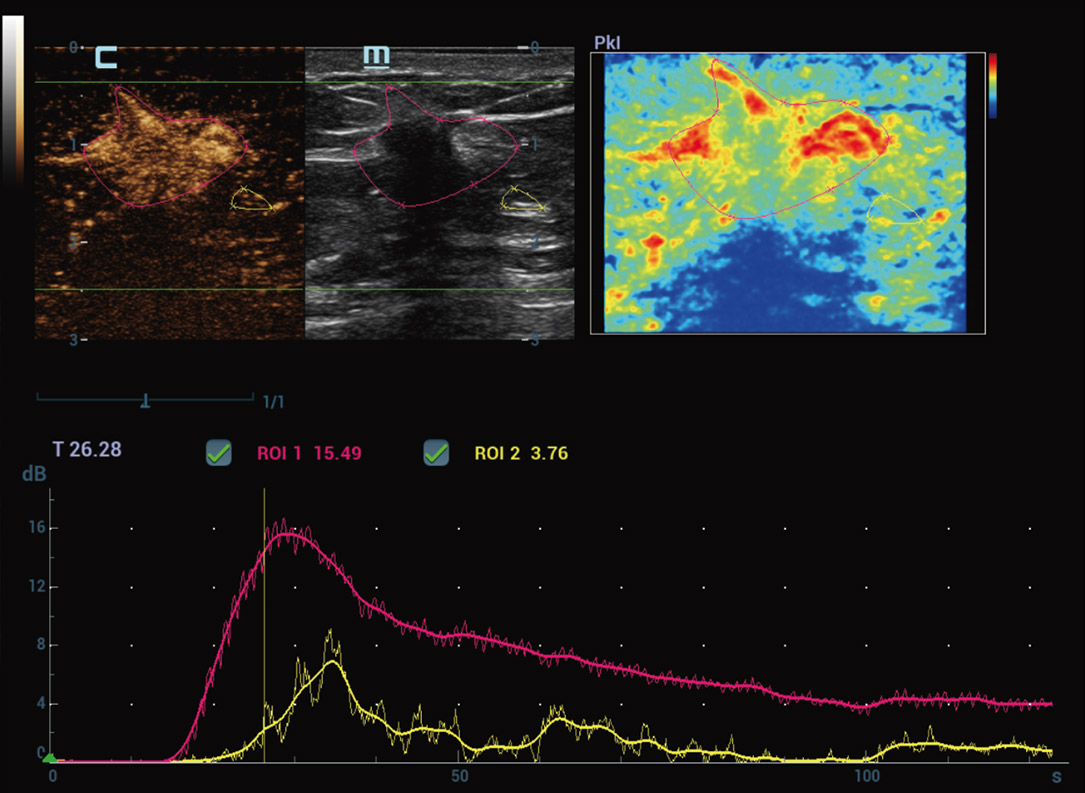

Nova anûÀlise de quantifica??o do CEUS

CEUS QA ã Tumor maligno de mama

A curva tempo-intensidade permite a anûÀlise quantitativa das imagens de CEUS. A nova QA CEUS fornece ferramentas de anûÀlise quantitativa de ponta para ajudar na avalia??o de tumores e na pesquisa clûÙnica.